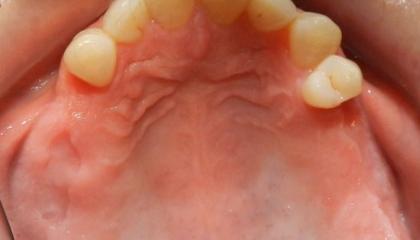

After

Zirconia bridge on Southern DC Implants